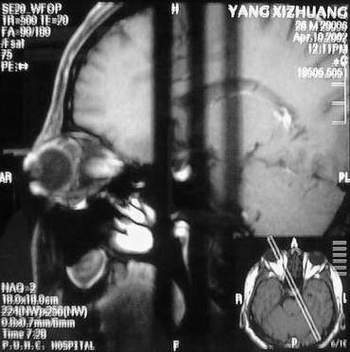

MRI及增强结果如下:

患者压颈及其它Valsava试验结果阴性。从MRI分析,在T1、T2、T+C检查该支血管均为明显流空现象,说明该血管血流速度很快,而从走行和分布看,眼上静脉可能性很大。也许也不能除外异常的眼动脉或异常血管。眶内主要可能的血管病变包括颈内动脉海绵窦瘘(高流窦)、AVM、眼眶静脉曲张、海绵状血管瘤、静脉性血管瘤、毛细血管瘤和眶内动脉瘤。。

根据MRI显示眼上静脉扩张可能性很大。眼上静脉扩张有几种原因:1.颈内动脉海绵窦瘘,2.眶尖肿瘤,3.甲亢,4.炎性假瘤.病人球结膜充血示静脉回流障碍,动脉瘤可能性小.根据病史,我认为排除1,2.则考虑3,4.查T3,T4.激素作诊断性治疗.